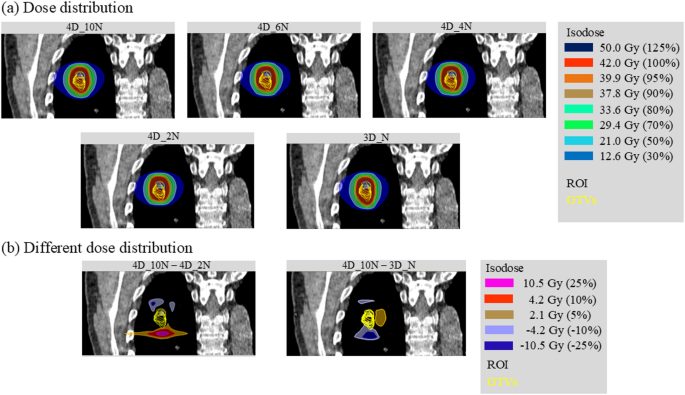

For all patients, SBRT plans with the helical tomotherapy technique were created using photon energy of 6 MV, a field width of 2.5 cm, a pitch of 0.108, and a delivery time factor of 1.331 and a collapsed cone convolution dose engine with a dose grid size of 1 mm in the RayStation. A nominal dose of 42 Gy in four fractions was prescribed to the GTV32. Four 4D robust optimization strategies were assessed using different CT phase sets for treatment planning: (1) all ten 4D-CT phases; (2) six phases (20%, 30%, 70%, 80%, end-expiration, and end-inspiration) (3) four phases (30%, 80%, end-expiration, and end-inspiration) (4) two phases (end-expiration and end-inspiration). This phase selection was based on a previous study32 and our assumption that the two extreme phases plus representative mid-phases adequately capture target motion. Each plan was optimized by minimizing the worst-case scenario dose distribution across the specified 4D-CT phases, targeting robust GTV coverage against a setup uncertainty of 5 mm in six directions: left, right, anterior, posterior, superior, and inferior. The optimization problems were identical for all plans, with the goal of 100% of the GTV receiving at least 48 Gy. OARs, such as normal lung, spinal cord, heart, and esophagus, were included in the 4D optimization. Dose constraints followed a previous recommendation32: lung V15Gy < 25%, lung V20Gy < 20%, lung Dmean < 18 Gy, spinal cord Dmax < 25 Gy, heart D15cc < 30 Gy, esophagus D1cc < 40 Gy, and D10cc < 35 Gy. To maximize OAR sparing without compromising target coverage, we adjusted dose objectives and weights while keeping parameters identical for each patient. Notably, the robust objective was applied only to the GTV; no specific constraints were imposed on OARs in this study. All plans were normalized after optimization, and 100% of the GTVs received 130% of the prescription dose. These plans are referred to as the nominal plans for (1) 4D_10N, (2) 4D_6N, (3) 4D_4N, and (4) 4D_2N. For the 4D_6N, 4D_4N, and 4D_2N plans, the nominal plans were recalculated for the unutilized phase CTs during the robust optimization to evaluate the dosimetric parameters for all-phase CTs. Figure 5a and b show the representative dose distributions of the four nominal plans and the different dose distributions between the 4D_10N and 4D_2N plans on the end-expiration phase CT in the coronal direction (patient Pt03).

Dose distributions. (a) Representative dose distributions for the five types of nominal plans on a coronal plane for patient Pt03. (b) Comparison of dose distributions between the 4D_10N and 4D_2N plans, and the 4D_10N and 3D_N plans in the coronal plane. GTV, gross tumor volume; ROI, region of interest.